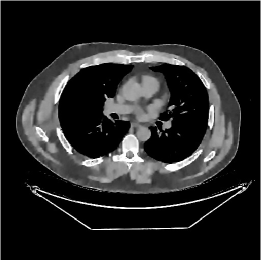

This section compares the reconstruction quality and runtime among the proposed MBIR method, PWLS-ST-, and other three MBIR methods, PWLS-EP, PWLS-DL, and PWLS-ST-. Table I shows that, for both 2D and 3D sparse-view CT reconstructions of the XCAT phantom, the proposed PWLS-ST- model outperforms PWLS-EP and PWLS-ST- in terms of RMSE. In addition, PWLS-ST- using a square transform (of size ) achieves lower RMSE than PWLS-DL using an overcomplete dictionary (of size ) for 2D sparse-view reconstructions. Fig. 3(a) and Fig. 4 show the reconstructed images for 2D and 3D phantom experiments, with different reconstruction models and different number of views. (See the corresponding error maps in the supplement.) The proposed PWLS-ST- consistently gives more accurate image reconstructions compared to other MBIR methods. Specifically, PWLS-ST- has smaller errors in the heart region (see zoom-ins in Fig. 3(a)) of 2D reconstructions than PWLS-DL and PWLS-ST-. In addition, compared to PWLS-ST-, PWLS-DL and PWLS-ST- have some ringing artifacts around the edges with high transition, e.g., edges between air and soft tissues. (See a comparison of profiles of PWLS-ST- and PWLS-ST- in the supplement.) In particular, PWLS-ST- and PWLS-DL give more visible ringing artifacts for 2D reconstruction from fewer views, and PWLS-ST- has these ringing artifacts for 3D reconstructions regardless of the number of views (see zoom-ins in Fig. 4). Table II reports runtimes of different MBIR methods in reconstructing the -views XCAT phantom scan. (FBPConvNet is a non-MBIR method and its runtime for processing a image is approximately one second with a TITAN Xp GPU.) While providing better reconstruction quality, the proposed Algorithm 1 of PWLS-ST- has shorter runtime compared to the algorithms of PWLS-DL and PWLS-ST- in Section III-A. Similar to the PWLS-EP algorithm, the reconstruction time of the PWLS-DL, PWLS-ST-, and PWLS-ST- algorithms can be further reduced by using ordered subsets [51].

Fig. 3(b) shows that when tested on the clinical scan data, the proposed PWLS-ST- method improves reconstruction quality in terms of noise and artifacts removal (e.g., see zoom-ins for soft-issue regions), and edge preservation (e.g., see zoom-ins for bone regions), compared to PWLS-EP and PWLS-ST-. Compared to PWLS-DL, PWLS-ST- achieves comparable image quality, but requires less computational complexity.

The benefit of the proposed PWLS-ST- over PWLS-ST- can be explained when there exist some outliers for some : in (12) gives equal emphasis to all sparse codes – from small to large coefficients that generally correspond to edges in low- and high-contrast regions, respectively – in estimating ; however, PWLS-ST- adjusts to mainly minimize the outliers, i.e., it may not pay enough attention to reconstruct regions with small coefficients. The histogram results in Fig. 1 reveal model mismatch of PWLS-ST- over the iterations. Fig. 3, Fig. 4, and Table I show that PWLS-ST- can moderate model mismatch, and provides more accurate reconstruction than PWLS-ST-.

| (a) 2D fan-beam CT experiments |

| (b) 3D axial cone-beam CT experiments |

III-B3 Generalization Capability Comparisons between a “Denoising” Deep NN and the Proposed PWLS-ST- Method

This section compares the generalization capabilities between the proposed MBIR method, PWLS-ST-, and a denoising deep NN, FBPConvNet [14], that are trained from the phantom data; in particular, we tested the trained PWLS-ST- and FBPConvNet models to phantom and clinical scan data. The results in Fig. 6 show that the non-MBIR FBPConvNet method has higher overfitting risks, compared to the proposed PWLS-ST- MBIR method. When tested on clinical scan data, PWLS-ST- achieves much more accurate reconstruction, compared to FBPConvNet. See Fig. 6(b). When tested on phantom data, FBPConvNet generates more unnatural features as the number of views reduces, although it gives lower RMSE values compared to PWLS-ST-. See zoom-ins in Fig. 6(a). The FBPConvNet results above correspond to those in the recent work [16] that FBPConvNet [14] generated some unexpected structures.